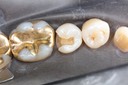

Larry Fujioka #12-13 pre-op